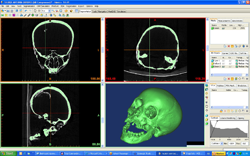

Az 1991-ben a pécsi székesegyház altemplomában végzett ásatáson megtalált férfi maradványait igen nagy valószínűséggel tekintik Janus Pannonius (1743-1772), Mátyás király humanista költő-püspöke földi maradványainak. A Magyar Természettudományi Múzeum Embertani Tárában (KUSTÁR ÁGNES antropológus és ÁRPÁS KÁROLY szobrászművész) elkészítették Janus Pannonius arcrekonstrukcióját. A koponyáról először CT- (Computer Tomográf) felvételt készítettünk a Semmelweis Egyetem Radiológiai és Onkoterápiás Klinikáján.

A koponya CT felvételéből készült 3D rekonstrukció |

|

Ezt követően 3D nyomtató készülékkel ”kinyomtattuk” annak műanyag térbeli másolatát, amelyre elkészítettük az arcrekonstrukciót.